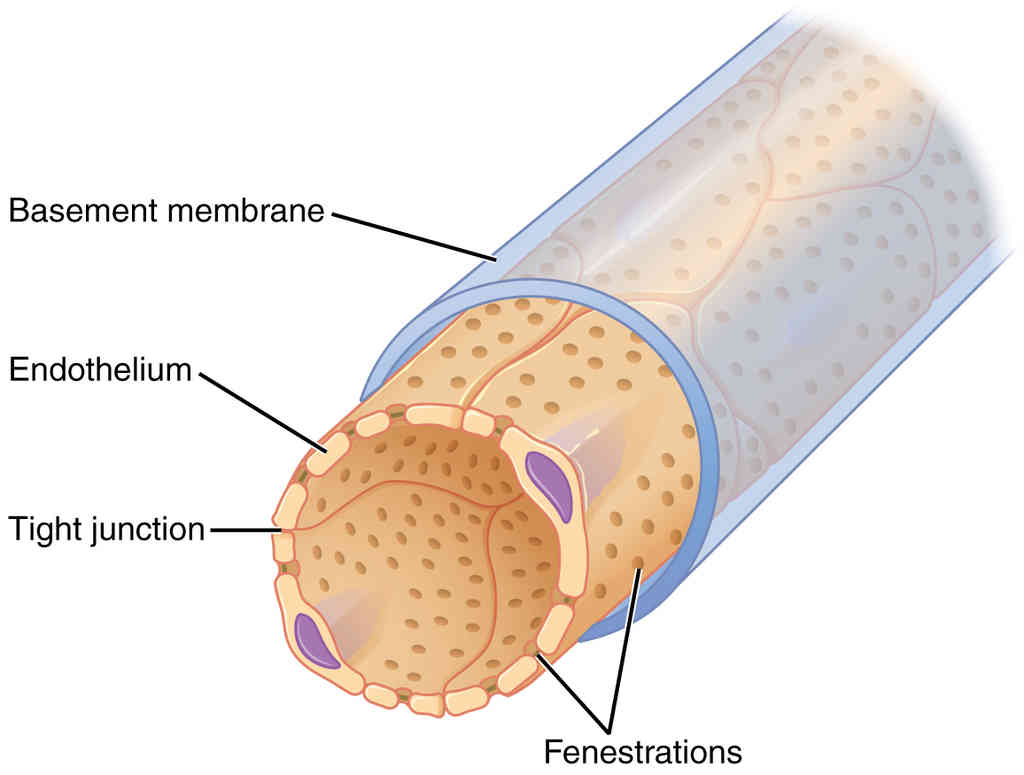

This page is under construction. For now, it is just a resource of the images found in the OpenStax Anatomy and Physiology Handbook. It wil slowly change into a revision tool. Each slide has a number. Use this to refer to the slide. When completed, it will have an unlabelled section, with labelled slides in parallel. On the unlabelled slides, write your answer and use the labelled slide to assess yourself. Keep track by also noting the number on each slide. Improvement at each attempt is important, more so than full marks on a first attempt.